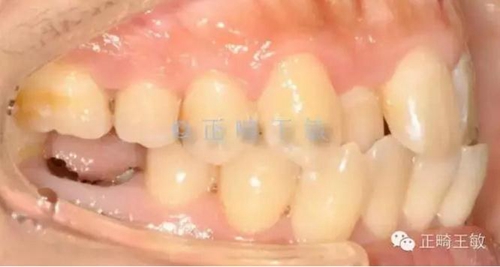

首先來(lái)看這樣一個(gè)病例:

這樣的情況看起來(lái)很復(fù)雜,缺2個(gè)牙,三類關(guān)系,擁擠,又偏又反。如何處理?